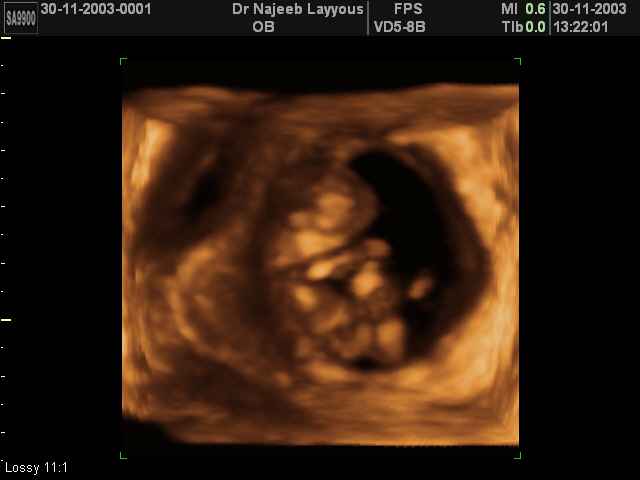

- First Trimester Ultrasound Photos

3D First Trimester Ultrasound Scan Photos ( Early Pregnancy Ultrasound Photos ) | Dr N Layyous